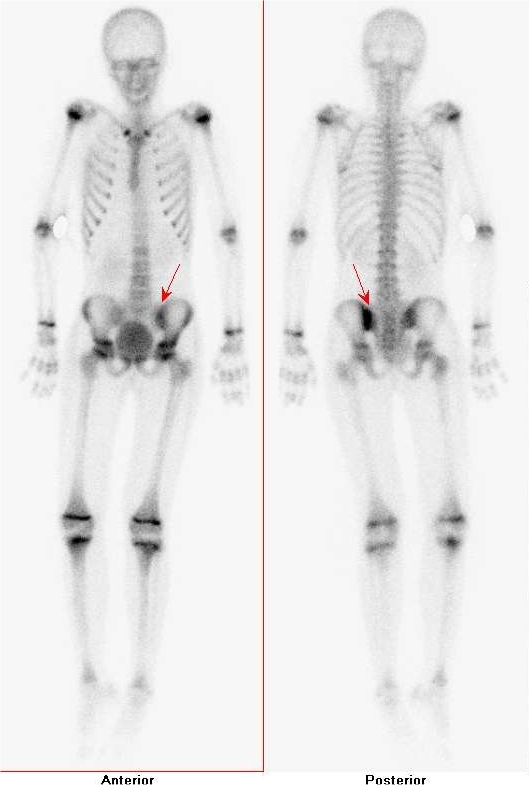

/ Obr. č. 2: Třetí skeletální fáze s patologicky zvýšenou akumulací

99mTc-HDP v levém SI skloubení – levý obrázek je z přední, pravý ze zadní projekce.

/ Obr.č.3: Celotělová scintigrafie skeletu v přední a zadní projekci - patologicky zvýšená akumulace

99mTc-HDP v levém SI skloubení,

fyziologicky zvýšená akumulace v růstových zónách dlouhých kostí.